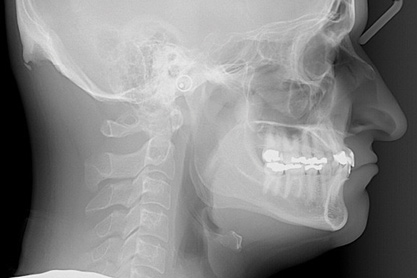

Fig 5. Preoperative cephalometric view highlighting maxillary deficiency, brachycephalic craniofacial phenotype, short upper face height, and maxillary retrognathia. Thin facial bone and proclined incisors are also noted.

Figure 5